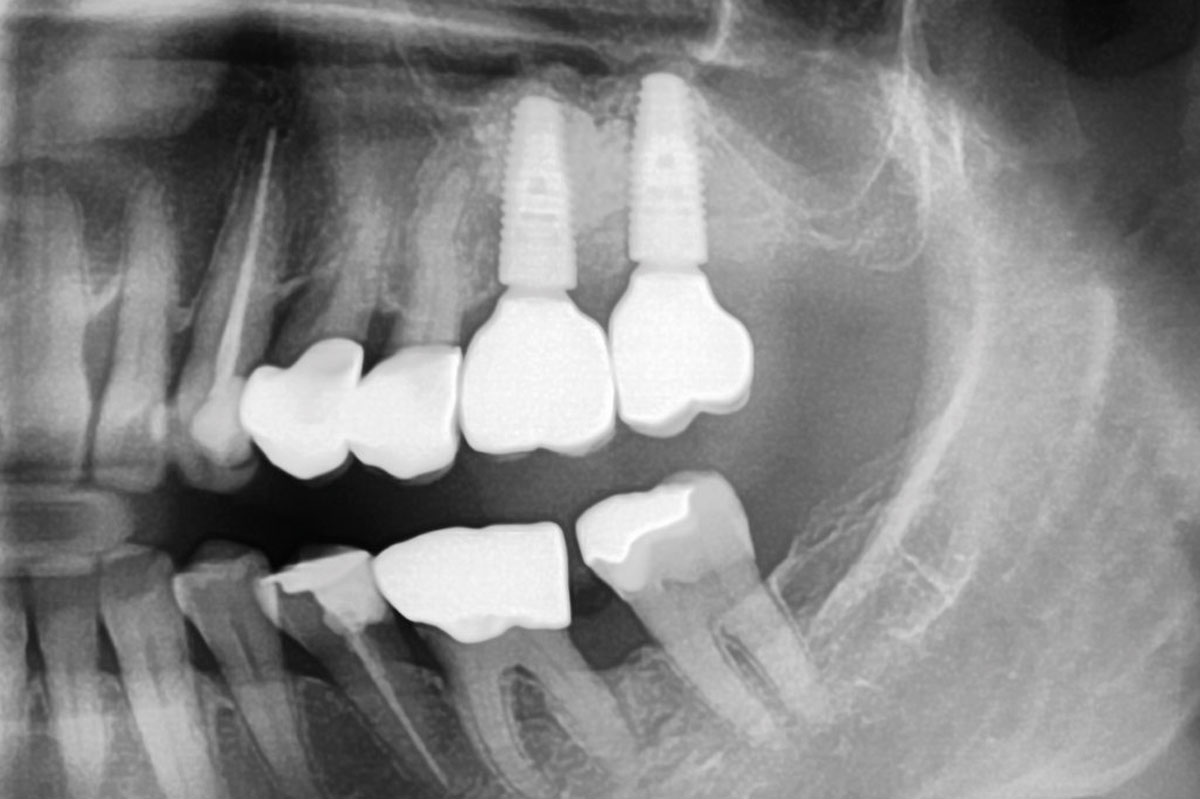

2/15 - Preoperative OPG displaying the vertical bone defectTreatment of a combined horizontal and vertical bone defect in the maxilla with maxgraft® cortico in the allogenic shell technique - Dr. R. Würdinger

3/15 - Preoperative OPG - planning of the implant placementTreatment of a combined horizontal and vertical bone defect in the maxilla with maxgraft® cortico in the allogenic shell technique - Dr. R. Würdinger

15/15 - X-ray control after final prosthetic restoration six months after augmentationTreatment of a combined horizontal and vertical bone defect in the maxilla with maxgraft® cortico in the allogenic shell technique - Dr. R. Würdinger